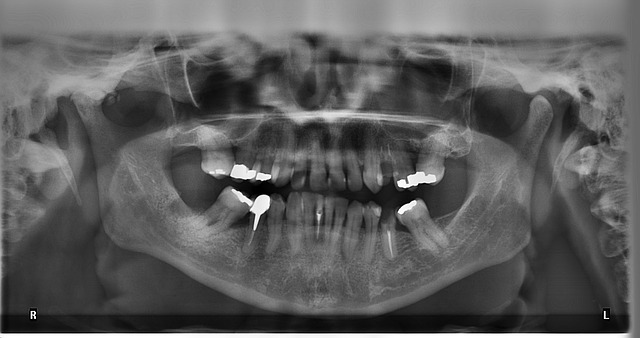

La plaque dentaire est une sorte de pellicule invisible qui se colle et s'accumule au fur et à mesure sur les dents tous les jours. Lorsque cette plaque dentaire n'est pas enlevée quotidiennement, elle se calcifie et forme un dépôt dur, ce qu'on appelle le tartre. Le tartre s'accumule de plus en plus sur nos dents avec le temps. L'accumulation de plaque et de tartre peut engendrer une maladie des gencives (gingivite) et de l'os qui supporte les dents (parodontite). Le tartre ne peut être délogé que par un nettoyage chez le dentiste, couramment appelé le détartrage.